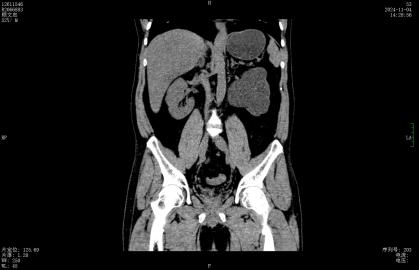

今年8月起,左腰部酸胀频繁不适,这才想起医生曾经的叮嘱,后找到深圳市罗湖区人民泌尿外科姜刚刚副主任医生门诊就诊,行CT检查发现整个左肾重度积水,而结石仍旧卡在输尿管内,最终只能无奈手术切除没有功能的左肾。